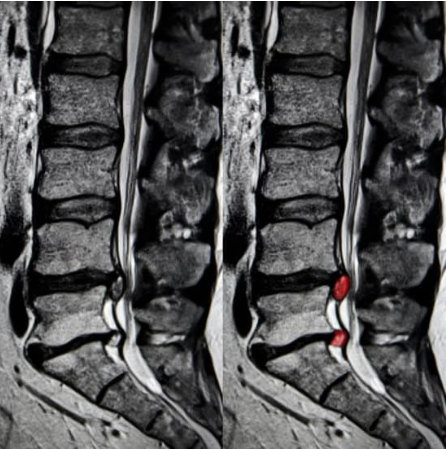

腰骨と腰骨の間には椎間板というクッションがあり、骨同士がぶつかるのを防いだり、腰骨を安定化させたりしています。しかし、時に椎間板の後ろに裂け目が入り、椎間板の中身(髄核)が後ろに飛び出し神経を圧迫し、腰痛や足のしびれ痛みを生じてしまうことがあります。これを腰椎椎間板ヘルニアと言います。ヘルニアは英語で飛び出すと言う意味なので、文字通り腰骨の椎間板が飛び出すことで起きる病気です。20-40歳の男性に多く、症状は様々で腰痛のみの場合や足のしびれ痛み(太ももの外側や後ろ側、ふくらはぎ)、さらにひどいと足の力が入らなくなったり、オシッコがでなくなったりすることもあります(この場合は緊急手術が必要)。症状が悪化する前に早期診断することが必要です。

まず診察を行います。腰や足のどの場所が痛いのかしびれるのかを確認します。またどのような姿勢で痛むのか、日常生活でどんな時がつらいのかを確認します。次にレントゲンのチェックをし、骨の異常がないかチェックします。ヘルニアを強く考える場合は、MRIを撮影し確定診断を行います。